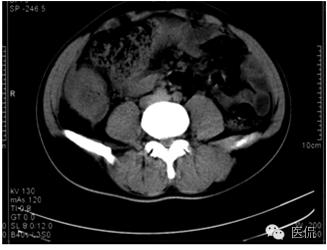

平扫示肝下缘局部隆突,密度减低,内部密度不均,隐约见分隔影,其下缘与升结肠界线消失,肠壁增厚、模糊。